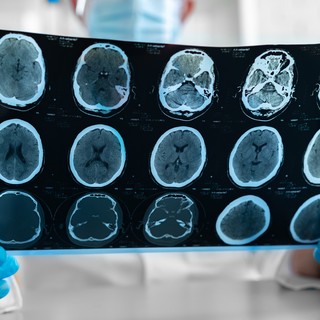

Az agyödéma különböző vizsgálatokkal diagnosztizálható, beleértve a neurológiai vizsgálatot, a CT-vizsgálatot, a fej MRI-vizsgálatát az ödéma mértékének és helyének meghatározására, valamint vérvizsgálatokat. A koponyaűri nyomás maga is mérhető katéterrel vagy szondával.

- CT

- MRI